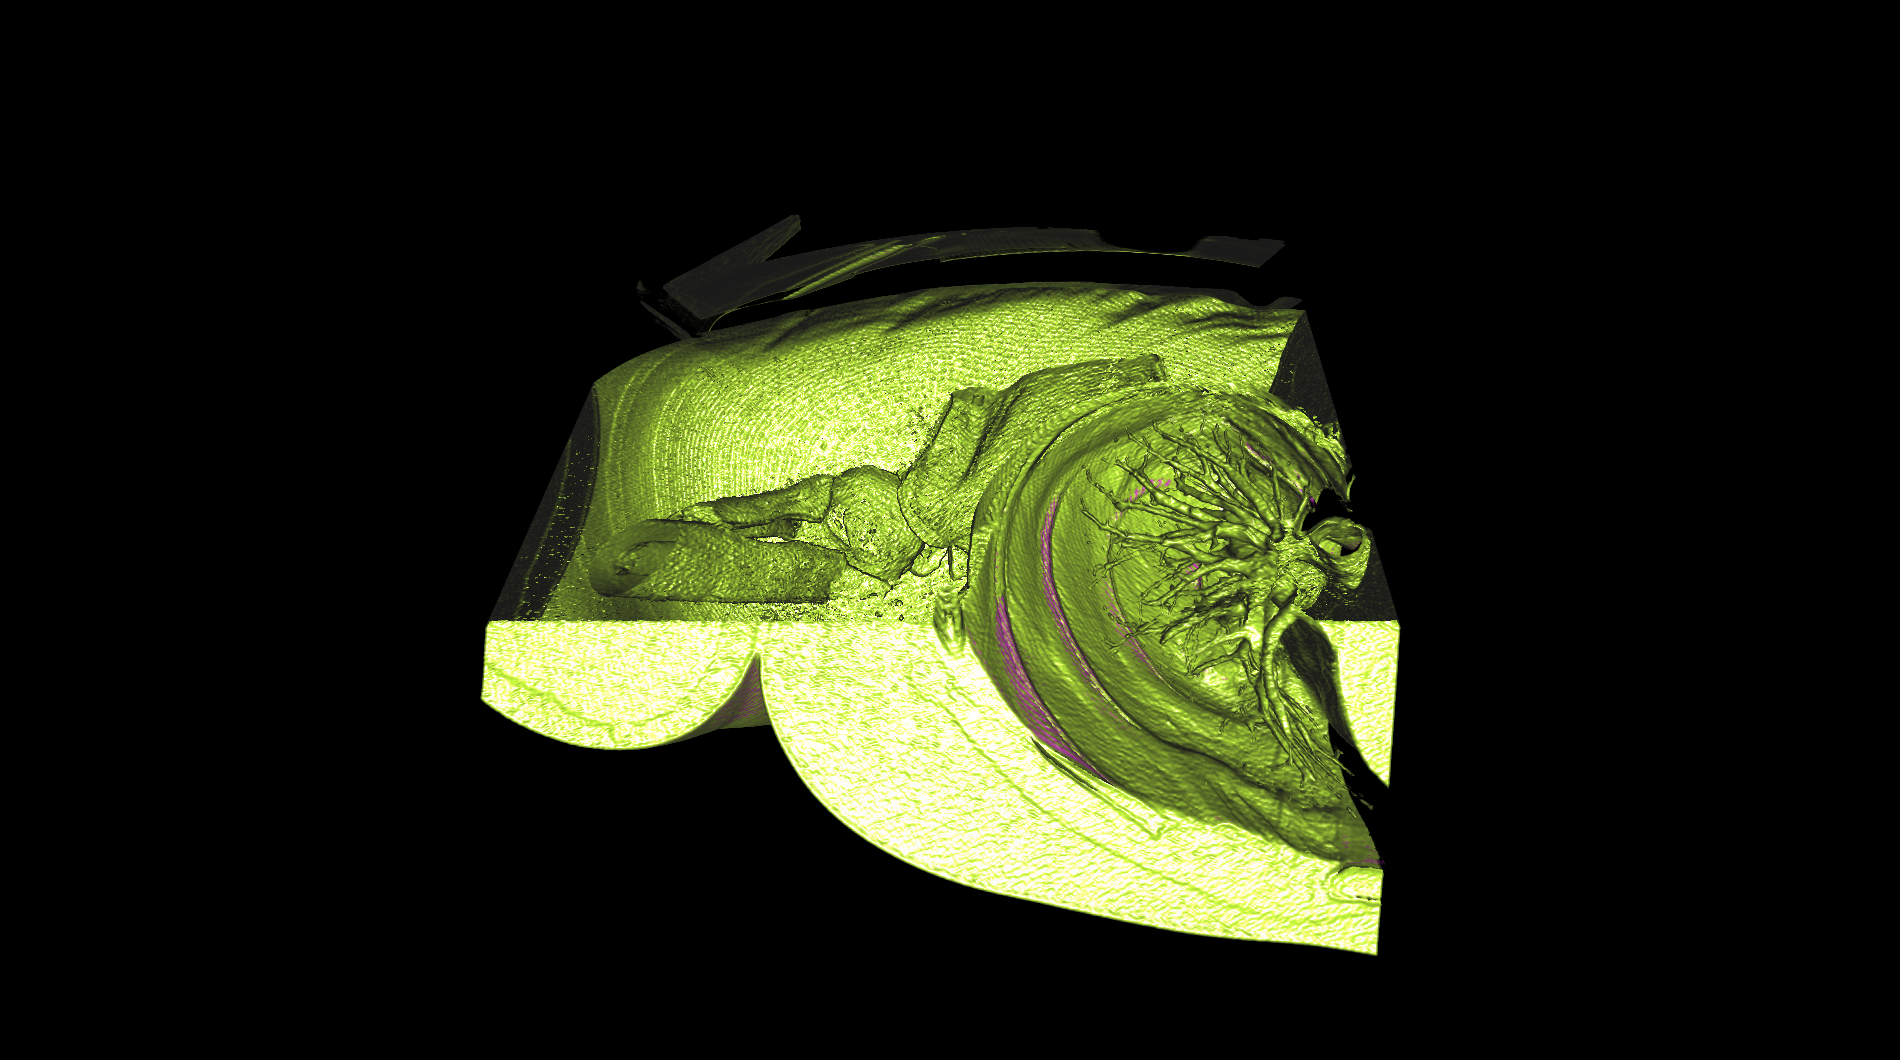

medical-03

The medical-03 viewset demonstrates the performance of several medical visualization volume rendering techniques. The first is "slice rendering", where many 2D slices are projected through the volume and composited on the screen. The second is "raycasting" where rays are projected through the volume accumulating the final pixel color. Two different transfer functions are used: 1D, where the density is used to look up each voxel color, and 2D, where density and gradient magnitude are used to look up each voxel color. A clipping plane is used in several tests. The Tuvok visualization library is used for rendering.

medical-03 composite score: 25.67

The composite score is a weighted geometric mean of the subtest scores. See the table below for subtest weights and FPS scores for this run.

Subtest results

Click on each thumbnail image below to display the subtest's screen grab.

The results table above includes the details about each test within a viewset. Viewsets are often comprised of many tests which produce a frame rate. Frame rate is computed as the average Frames Per Second (FPS), or the total number of frames rendered divided by the time in seconds to render those frames. These FPS values are then used to compute the composite score using the weights for each test.